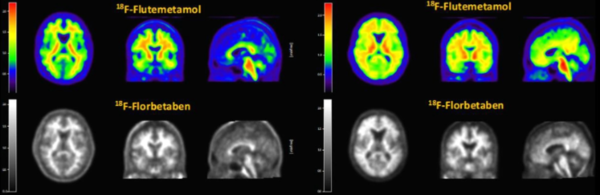

현재 아밀로이드 베타만을 표적해 이미지로 보여줄 수 있는 방법은 방사성의약품을 이용한 PET/CT 진단이 가장 많이 사용된다.